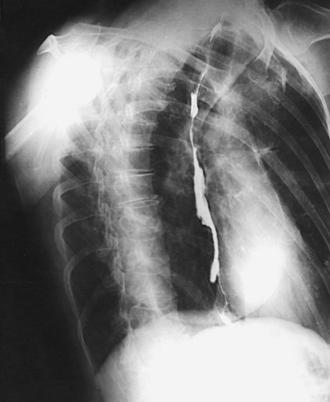

The esophagus lies just in front of the vertebral column, with its anterior surface in close relation to the trachea, aortic arch, and heart. This makes the esophagus valuable in certain heart examinations. When the esophagus is filled with barium sulfate, the posterior border of the heart and aorta are outlined well in lateral and oblique projections (Fig. 10-7). Frontal, oblique, and lateral images are often used in examinations of the esophagus. Radiography of the esophagus is discussed later in this chapter.

Fig. 10-7 A, PA projection of esophagus with barium sulfate coating its walls. B, PA oblique projection with barium-filled esophagus (RAO position).

Cardiac studies with barium: PA chest radiographs are often obtained with the patient swallowing a bolus of barium sulfate to outline the posterior heart and aorta. The barium used in cardiac examinations should be thicker than the barium used for the stomach so that the contrast medium descends more slowly and adheres to the esophageal walls. The patient should hold the barium in the mouth until just before the exposure is made. Then the patient takes a deep breath and swallows the bolus of barium; the exposure is made at this time (see Fig. 10-7).

Cardiac studies with barium: The left lateral position is traditionally used during cardiac studies with barium. The procedure is the same as described for the PA chest projection (see p. 508).

RAO position: The maximum area of the left lung field (side farther from the IR) is shown along with the thoracic viscera. The anterior portion of the right lung is superimposed by the spine (Figs. 10-45 and 10-46). Also shown are the trachea and the entire left branch of the bronchial tree. This position gives the best image of the left atrium, the anterior portion of the apex of the left ventricle, and the right retrocardiac space. When filled with barium, the esophagus is shown clearly in the RAO and LAO positions (see Fig. 10-46).

Barium studies: RAO and LAO positions are routinely used during cardiac studies with barium. Follow the same procedure described in the PA chest section (see p. 507).